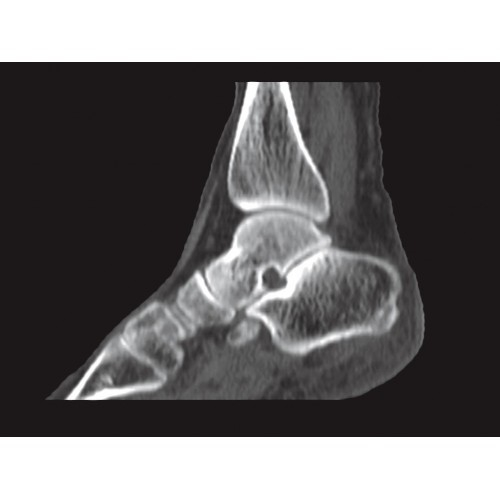

Позволяет проводить комплексные исследования всех анатомических зон, включая нейровизуализацию, ангиографию, исследования органов грудной и брюшной полости. Особенно эффективен для раннего выявления онкологических заболеваний.

Специализированные исследования

Обеспечивает высокую точность при кардиологических исследованиях, визуализации костных структур и суставов. Подходит для динамического наблюдения в ходе лечения.